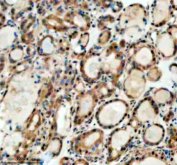

Immunohistochemical staining of SMARCAL1 using anti-SMARCAL1 antibody. SMARCAL1 was detected in a paraffin-embedded section of human thyroid cancer tissue. Heat mediated antigen retrieval was performed in EDTA buffer (pH 8.0, epitope retrieval solution). The tissue section was blocked with 10% goat serum. The tissue section was then incubated with 2 ug/ml rabbit anti-SMARCAL1 antibody overnight at 4oC. Peroxidase Conjugated Goat Anti-rabbit IgG was used as secondary antibody and incubated for 30 minutes at 37oC. The tissue section was developed using an HRP secondary and DAB substrate.